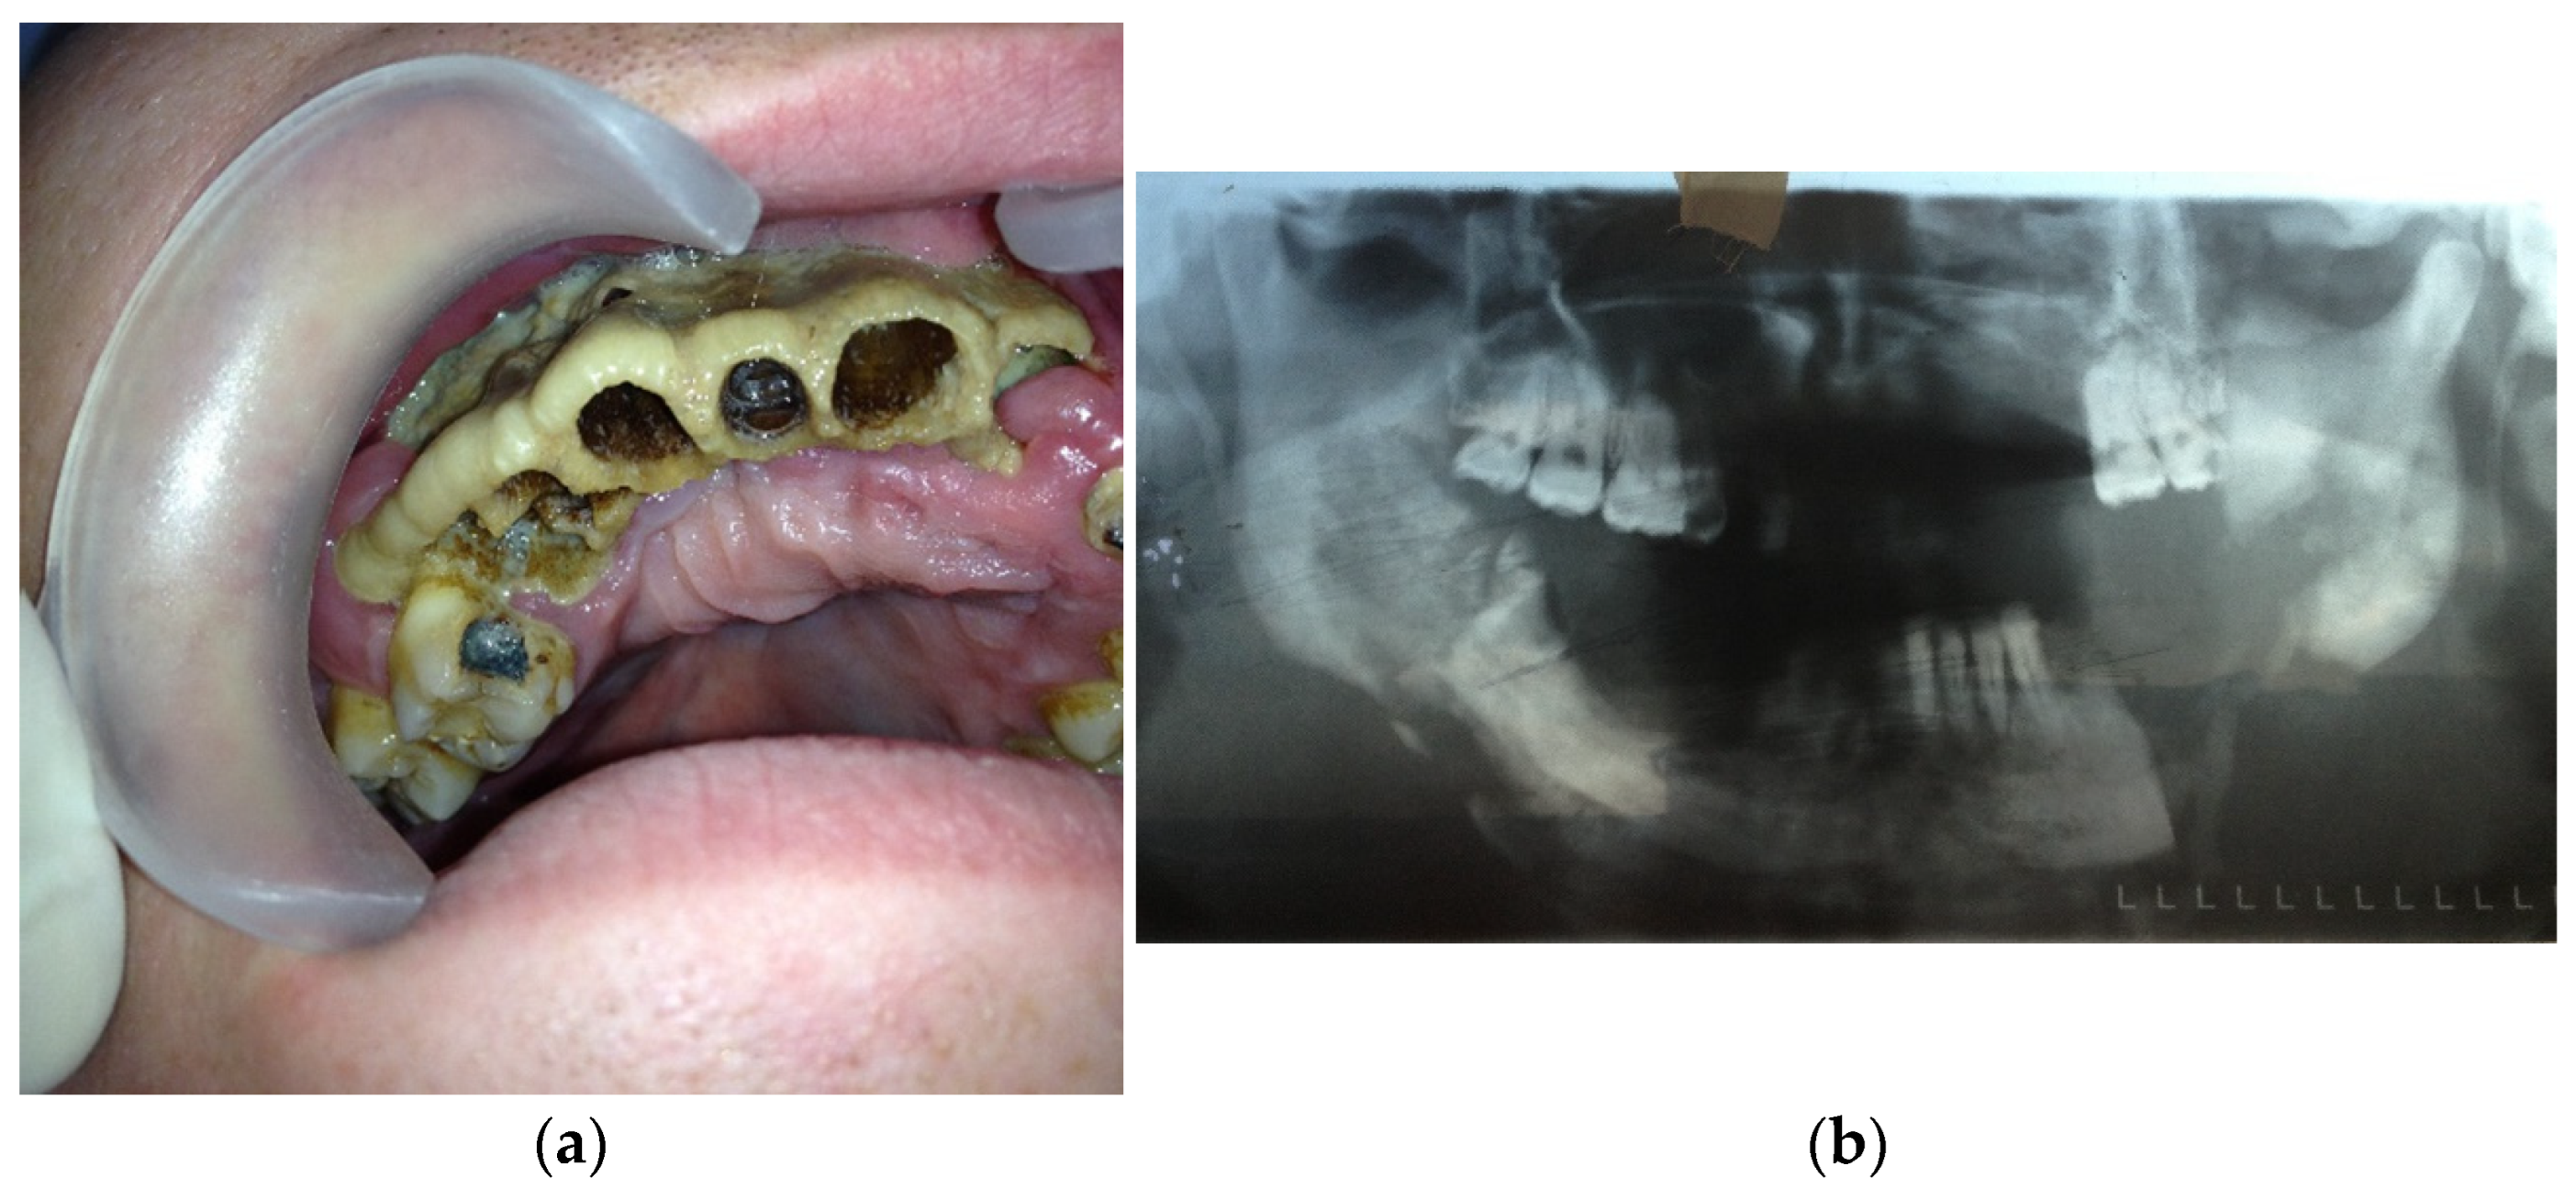

- Type 2: patients with maxilla involved (at least three teeth are included)—14 patients (28%) (Figure 2a,b);Figure 2. (a) Patient with type 2 toxic phosphorus osteonecrosis. Intraoral view; (b) patient OPG.